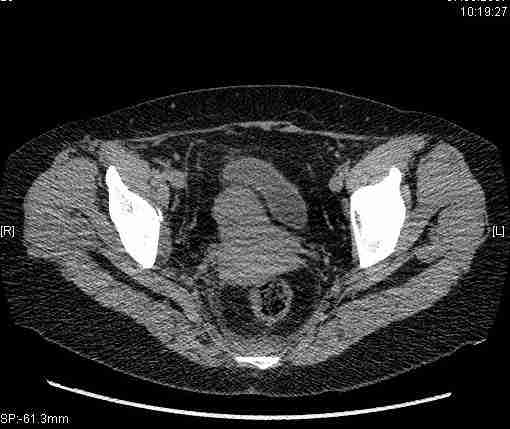

Женщина,58 лет, после ДТП 6 суток. Первично повреждение расценено как переломы ветвей лонной кости. После подтверждения повреждения вертлужной впадины,как чаще всего случается, вопрос встал о тактике. БОльшинство за консерватиное лечение.К сожалению кт у нас "во время" сломался. Прилагаю стандартные снимки вертлужки. У меня следующие вопросы к коллегам:1. Правильно ли рассценивать это повреждение как Т-образный перелом вертлужнй впадины?2. Можно ли добиться анатомической репозиции поверхности вертлужной впадины скелетным вытяжением в данном случае, если нет, что будет этому препятствовать?3. Если смещение останется таким как сейчас, через какое время появится необходимость эндопротезирования (по вашему опыту)?Спасибо.

Удалось сегодня вывести пациентку в соседнюю больницу, где есть кт. Срезы сделаны только горизонтальные.

Следом 3d